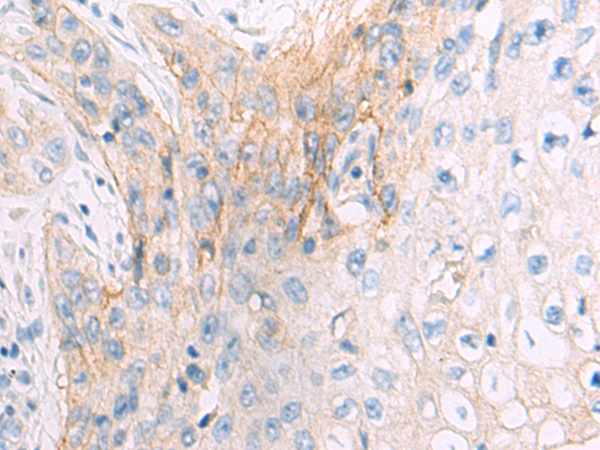

分类: 科研抗体货号: P00501别名: KIAP; LIVIN; MLIAP; RNF50; ML-IAP应用: WB,IHC反应种属: Human, Mouse